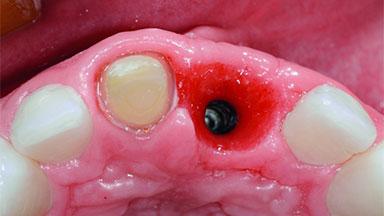

Replacement of an Ankylosed Upper Left Central Incisor: Bone Augmentation and Socket Grafting, Late Placement of an RC Bone Level Implant

A 15-year-old male patient was referred to us by his pediatric dentist in June 2004 for evaluation of treatment options for his failing tooth 21. The patient had recently seen an endodontist for internal bleaching and been advised that there had been significant resorption and ankylosis. The patient’s mother was concerned because the tooth appeared shorter than the adjacent one. His past dental history was significant for trauma (September 2001), where the tooth had been avulsed and reimplanted. Teeth 11 and 21 had been endodontically treated.

Bone Augmentation Horizontal|Simultaneous|Staged

Augmentation Materials Autogenous chips|Xenogenous

Bone Volume Deficient horizontally, requiring prior grafting